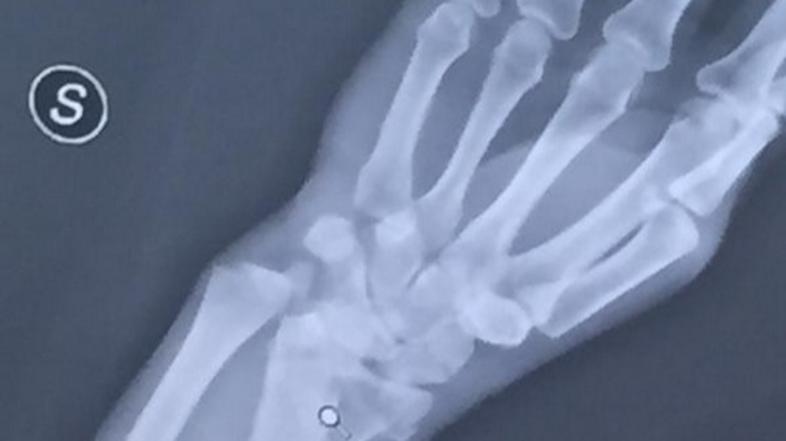

Sally Pearson rengenska slika Reševalni pas/Twitter

Olimpijski zmagovalka na 100 metrov z oviramo Sally Pearson je v začetku meseca grdo padla med tekmo diamantne lige v Rimu. Sedaj je z oboževalci delila rentgenski posnetek njene "eksplodirane roke".

Avstralka Sally Pearson se ni le bala konca svoje uspešne kariere, ampak ji je celo grozila amputacija leve roke. Olimpijska prvakinja iz Londona  je med finalom teka na 100 metrov z ovirami padla in si pri tem hujše poškodovala roko.

"Prestrašila sem se, ko sem videla, da je roka kazala v napačno smer. Takoj sem pomislila, da mi jo bodo morali amputirati," je povedala Pearsona po padcu. Zdravniki so ji v bolnici nato povedali, da ji je zapestje tako rekoč "eksplodirala". Imela je več zlomov in morala večkrat na operacijo.